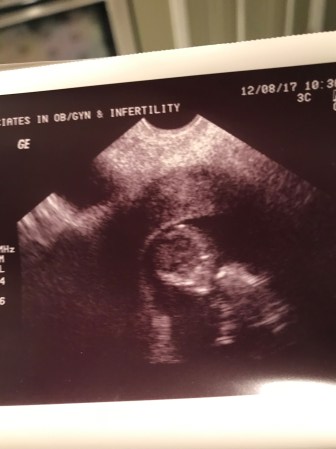

She did an ultrasound and though it was grainy, for the first time we saw the reflection of a baby on the screen. Our little girl! We were officially 12 weeks along and knew it was time to start sharing the news. This was becoming so real and wonderful. Acceptance continued to set in.